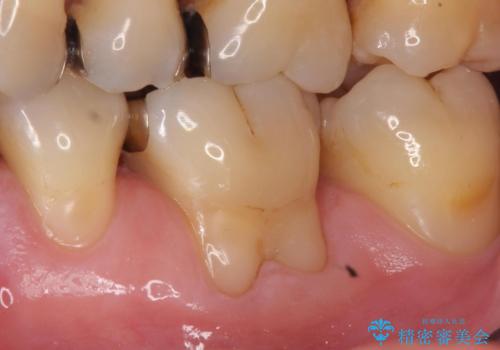

Dr. 岡田康成の症例写真

担当医 岡田康成<2025年1月10日更新>